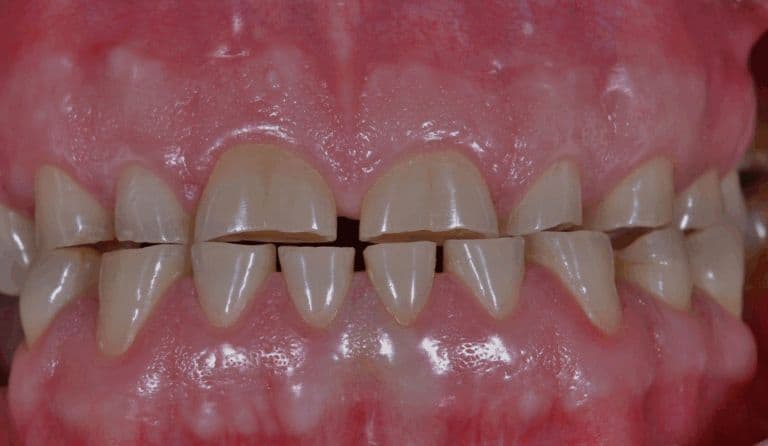

Real Success. Real Change